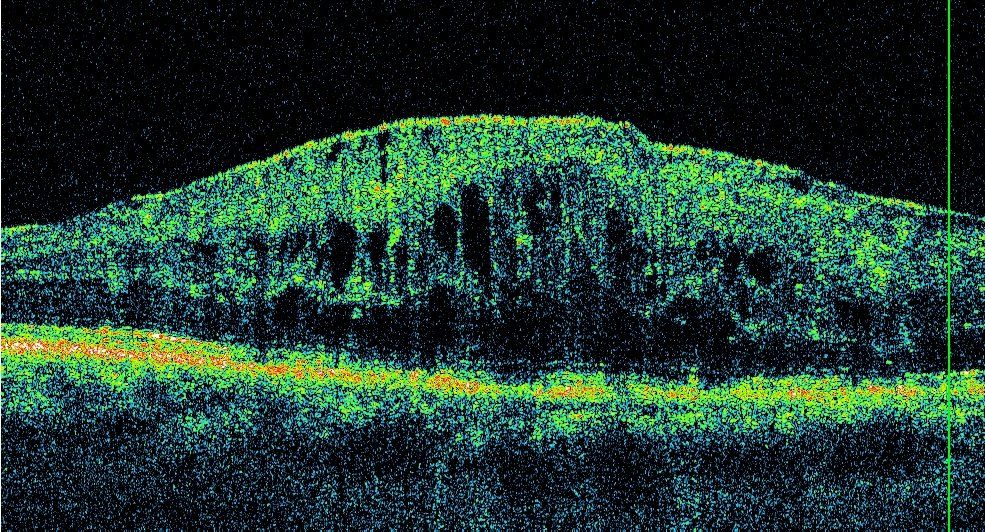

La tecnica trova largo uso in oftalmologia e ha numerose altre applicazioni biomediche. L'OCT sfrutta un raggio laser infrarosso analogamente a quello che fa un sonar con i fondali (a livello acustico), e riesce a ricostruire al computer la struttura Retinica, del Nervo Ottico e della Cornea, in due o tre dimensioni.

Consente, ad esempio, lo studio in sezione della Retina (Fig. 1a.b) e la diagnosi di eventuali patologie come DMS umida, Foro Maculare, Pucker Maculare, Edema diabetico e Edema infiammatorio, lo studio del nervo ottico e delle fibre nervose e quindi permette di fare una diagnosi precoce di glaucoma e di seguire poi l’evoluzione della patologia nel tempo.